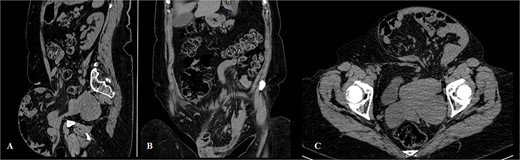

The physical exam revealed an irreducible giant abdominal wall hernia (mostly on the left lower part of the abdominal wall). Due to irreducibility, the hernia defect was not accessible for palpation and estimation. A previous low midline laparotomy scar was visible (Fig. 1A and B). A computerized tomography diagnostic scan of the abdomen was performed. It presented with a hernia defect (65 mm in width) in the left inguinal region (Fig. 2A–C).

Computerized tomography of the abdomen (A – sagittal scan, B – coronal scan, C – axial scan).